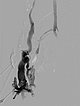

Röntgendurchleuchtung nach Direktpunktion der venösen Malformation während der Sklerosierungsbehandlung. Durch den Verschluss der Kommunikationsvenen mit dem tiefen Leitvenensystem ist die VM jetzt alleingestellt und kann sklerosiert werden. Nach Anspritzen kein Abstrom des Kontrastmittels mehr in die Leitvenen.